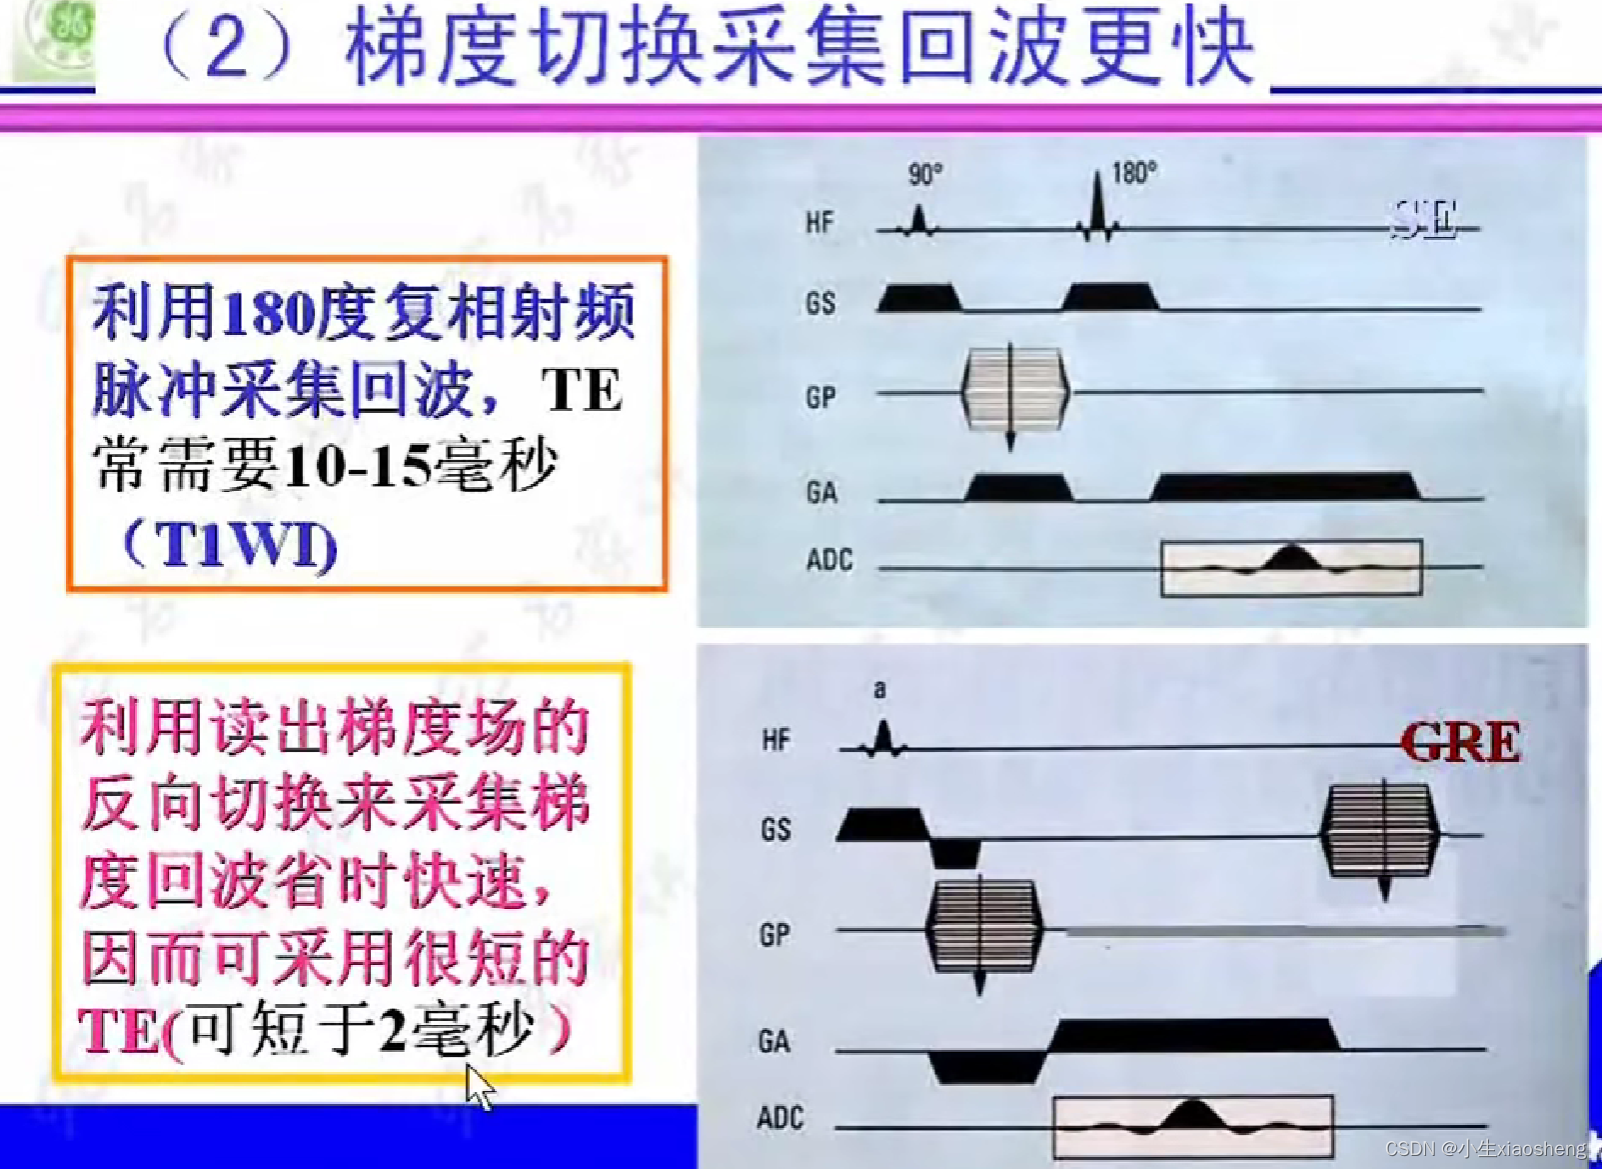

五、梯度回波类序列

GRE就是梯度回波